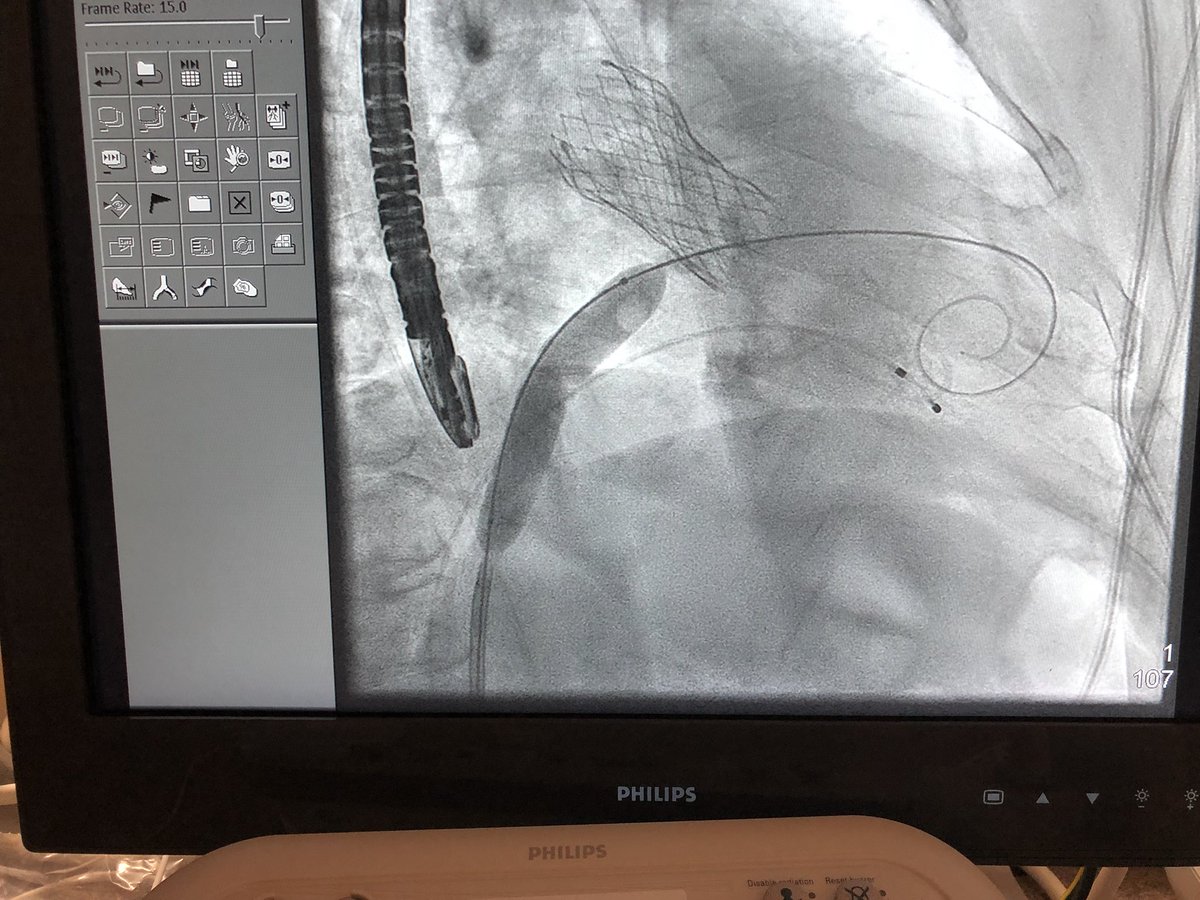

Septostomy with 14 mm balloon extra small safari in LV pointing downward Image

TMVR with 29 mm S-3